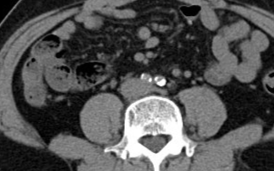

Relevant Test Results Prior to Catheterization

ABI measured on December 13, 2021, was 0.64on the right and 0.59 on the left. Duplex ultrasonography performed on August6, 2024, revealed monophasic flow in bilateral CFA, SFA, popliteal, ATA, andPTA arteries, favoring bilateral severe iliac artery disease. Subsequent CTangiography on November 15, 2024, demonstrated aortoiliac occlusive disease,without evidence of aneurysm or distal vessel obstruction. Laboratory databefore admission showed HbA1c 6.9% and LDL 76 mg/dL.

Diagnosticangiography revealed total occlusion of both common iliac arteries, while theexternal iliac arteries remained patent bilaterally. The lesions wereconsistent with aortoiliac occlusive disease (Leriche syndrome), and the distalflow was preserved via collateral circulation.